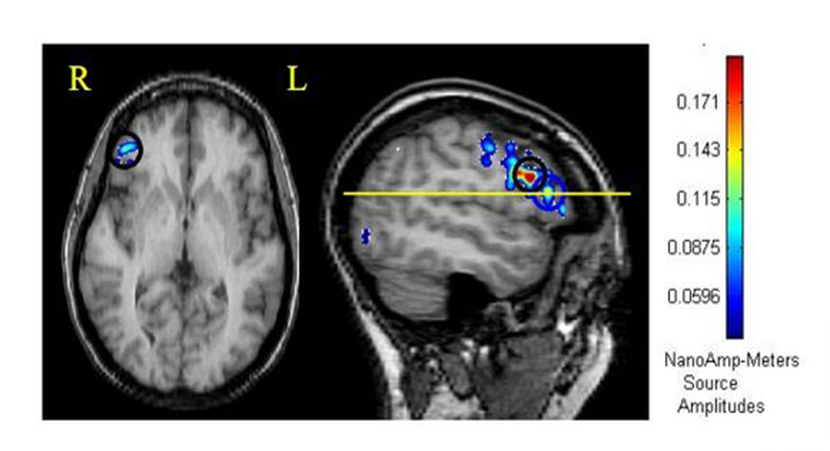

◆ 美国东卡罗来纳大学沟通科学与障碍系口吃研究小组中的三位成员Joseph Kalinowski, Ph.D., Andrew Stuart, Ph.D.,and Michael Rastatter, Ph.D历经数十年研究发现,口吃者在口吃时,脑波反应图与正常人脑波图有着明显的区别,言语时应该活跃的大脑左侧(言语语言中枢)变得不活跃,而应该静止的大脑右侧区域则变得活跃起来。

◆ 当口吃者佩戴延迟听觉反馈(DAF)/ 移频听觉反馈(FAF)设备后,其脑波反应图中的颜色几乎与正常人的均匀的兰色脑波图一致,难以区分,说明短促的数字延迟听觉反馈(DAF)/ 移频听觉反馈(FAF)可影响大脑的左、右半球的交流状态,有利于改变发音方式进行语言训练。